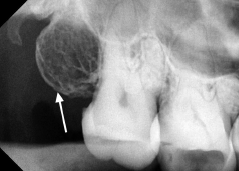

1. What is the anatomical structure indicated by the arrow in this radiograph?